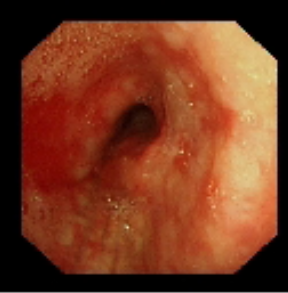

術前氣管重度狹窄